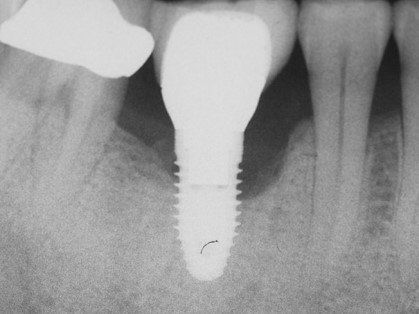

Для этого нами были изучены непосредственные и отдаленные результаты лечения периимплантита у 17 пациентов пародонтологического кабинета хирургического отделения АУЗ «РСП» в возрасте 24—56 лет (9 мужчин и 8 женщин) — основная группа — и 5 пациентов контрольной группы. Срок пользования имплантатами от 1 года до 7 лет, имплантаты как во фронтальных участках, так и в области премоляров и жевательных зубов (всего 24 имплантата). Не все пациенты обратились с жалобами (кровоточивость, отделяемое из десны, дискомфорт), у 5 пациентов (29,4±0,7 %) периимплантит был диагностирован во время осмотра. Диагноз периимплататный мукозит — у 2 пациентов, у остальных периимплантит, подтвержденный рентгенологически (рис. 1, 2) .

Рис. 1. Рентгенологическая картина периимплантита.

Рис. 2. Рентгенологическая картина периимплантита.